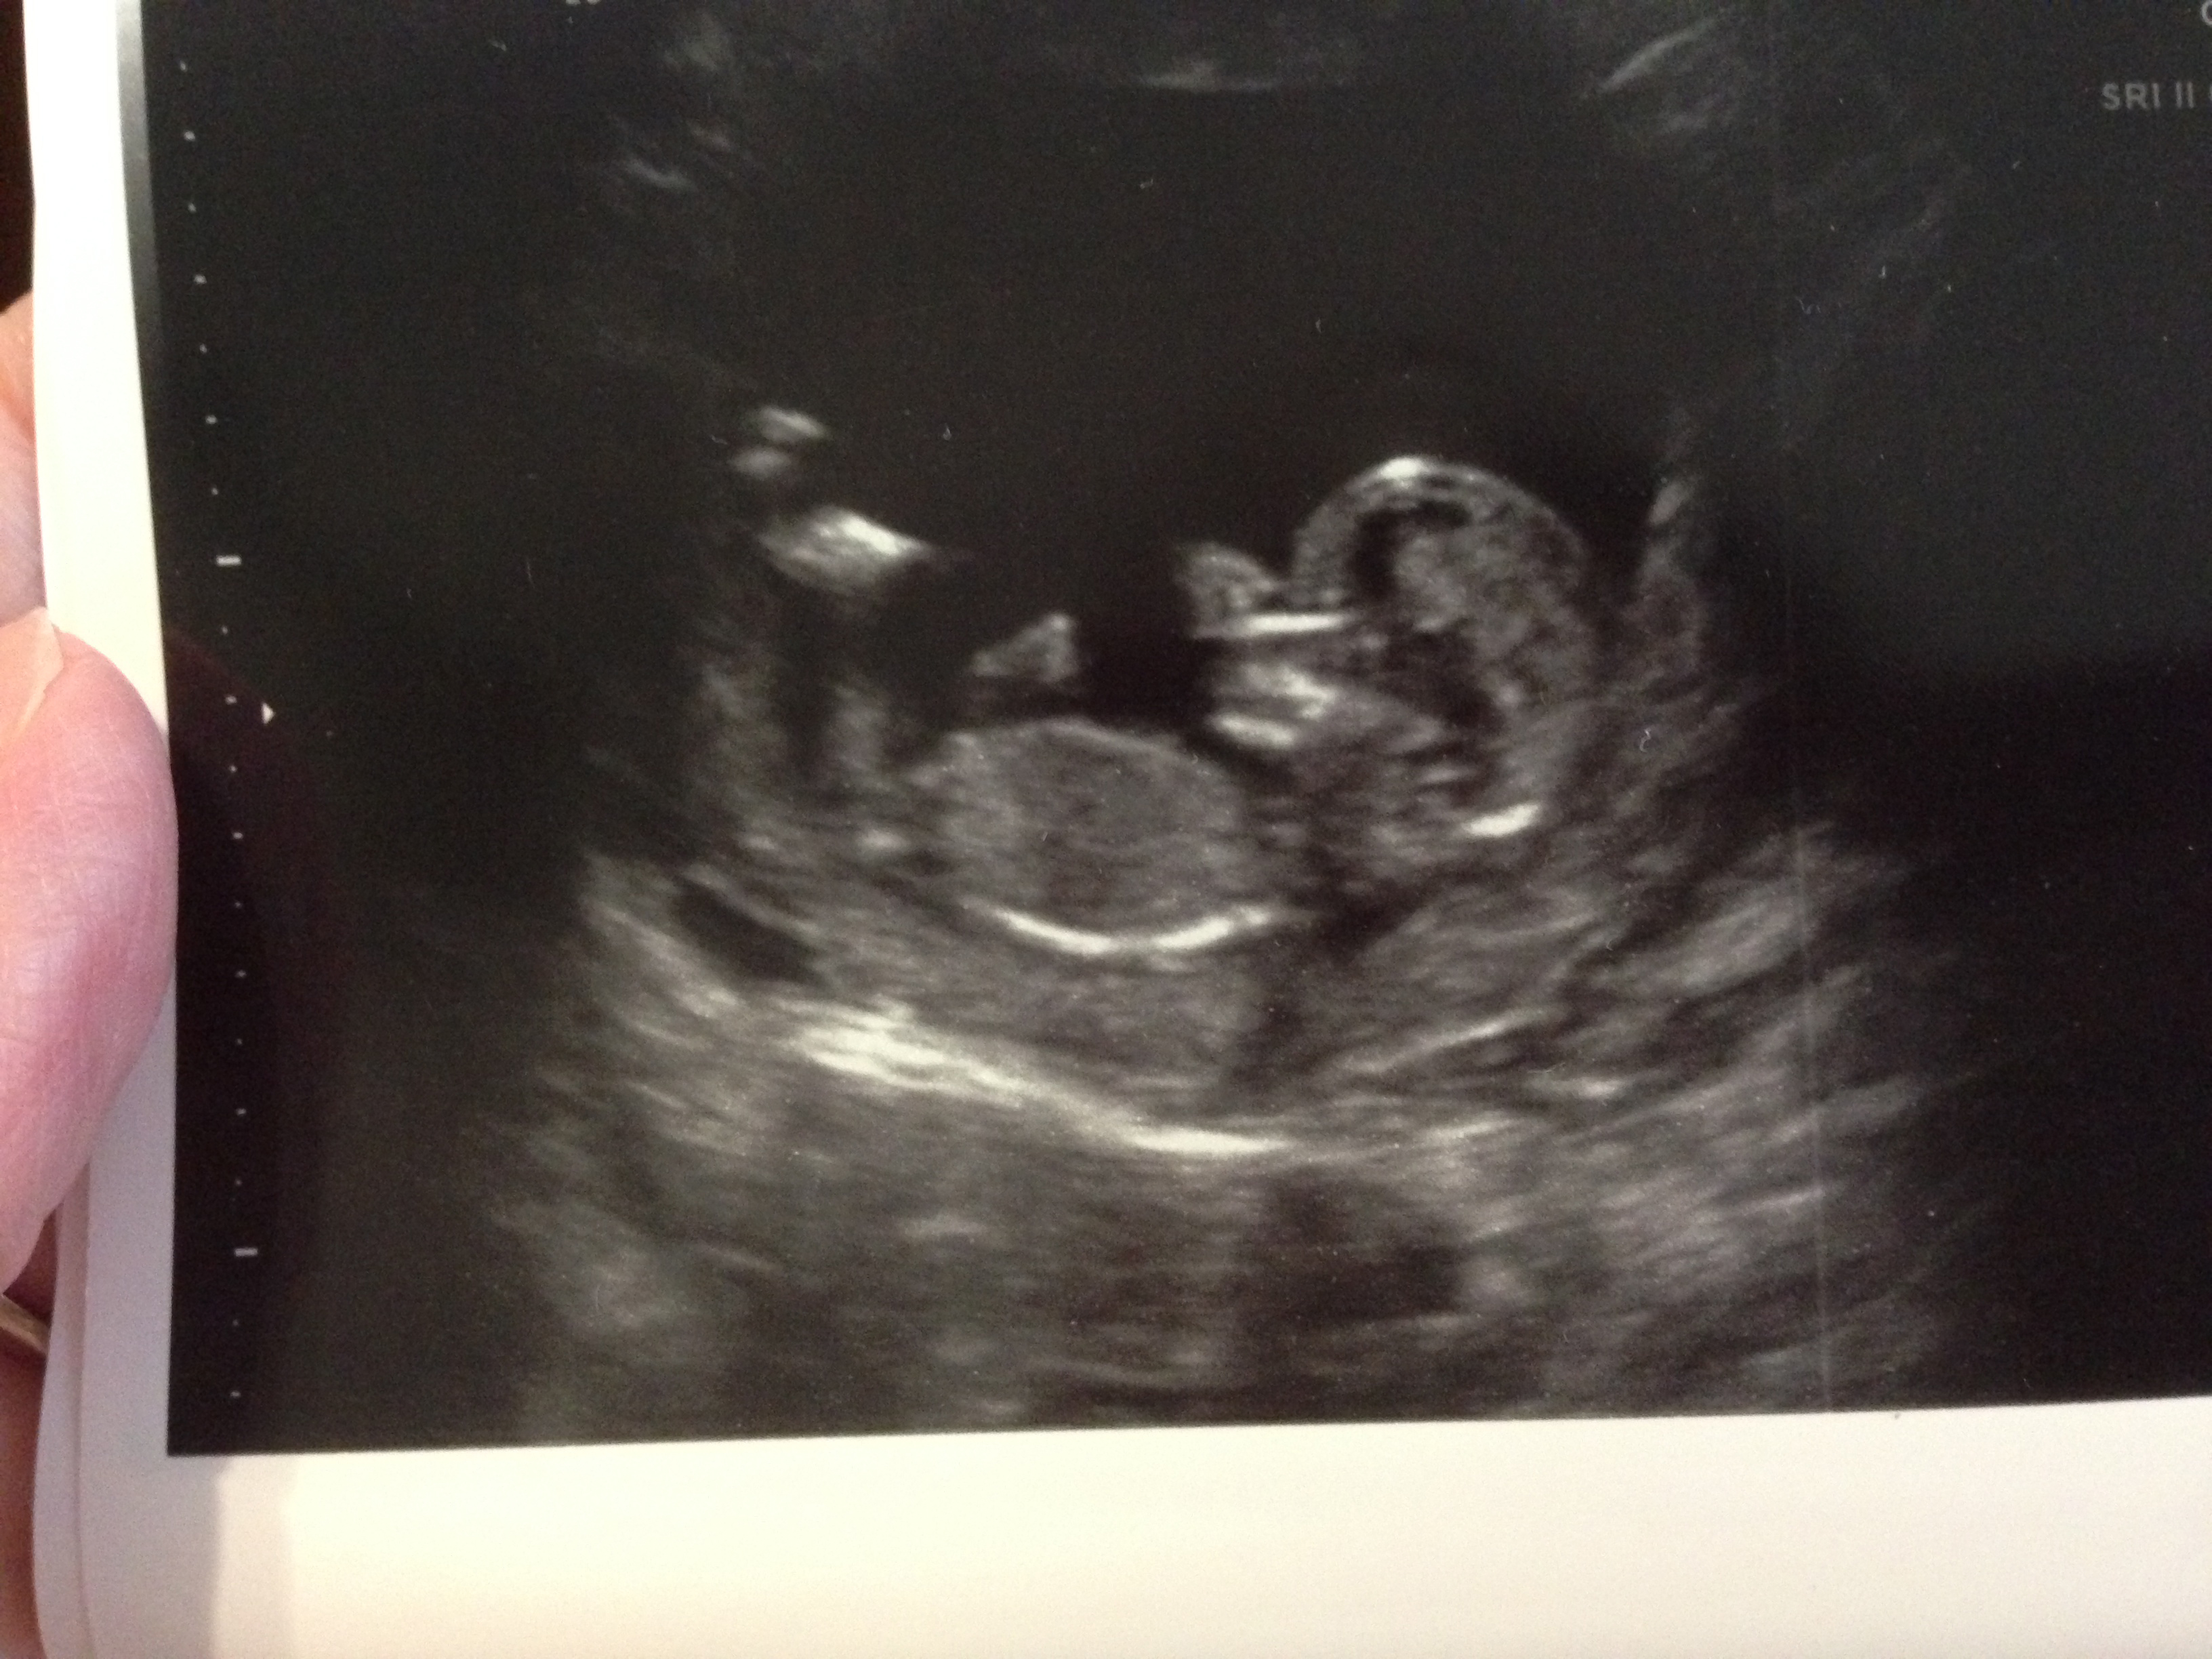

UPDATED --Just for fun, anyone want to take a guess

Just in case anyone wanted to compare skulls or potty shots (well upside down potty shot...lol....not the most reliable at that stage I'm sure), we got GIRL at today's ultrasound.  Anyone disagree?? :)

I know it's REALLY hard to tell at this stage, and we couldn't get a good nub shot :/  Tech "didn't believe in that stuff".  *shrug*.  Anyway.....she did do a potty look and there was nothing there, but she said it was still too early to see anything.  She did manage to print an over head shot of the legs AND a cool 3D shot that looks like there's a bulge there, BUT I know girls are really swollen at this age as well (most of the time still with a nub).  So thoughts?  Wanna guess?  I don't even care what it is one way or the other, I'm just impatient! ha! :)  We'll have to wait for a gender scan I guess to be sure :) I won't take what you say to heart, but I'd love some fun guesses :)

Attachment 19284Attachment 19284